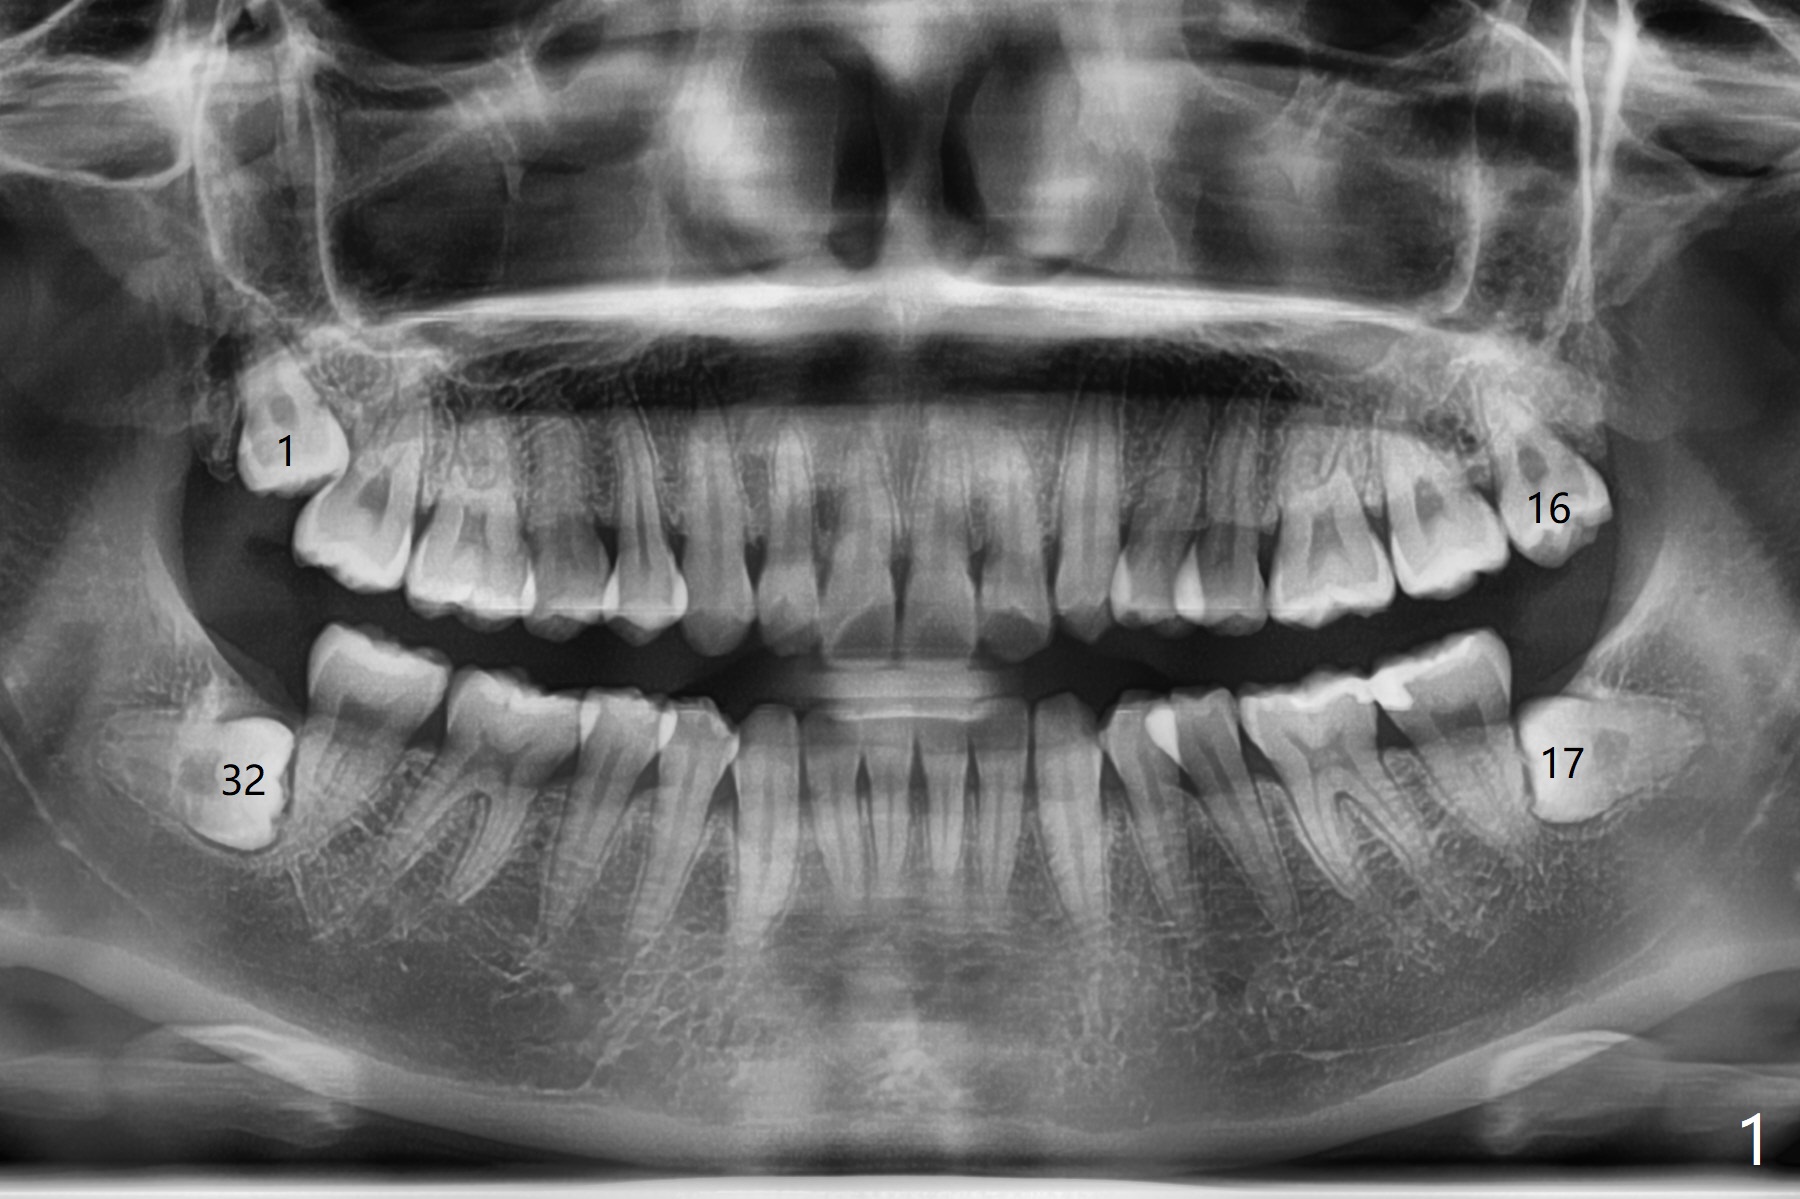

A 27-year-old woman (nervous) is going to return for #16 and 17 extraction (Fig.1). Offer sedative (Valium) if she cannot overcome fear. Take PAs for #17 and 32 to confirm Buccal Impaction, which dictates position of the accessory incision to reduce loss of bone graft in case of wound dehiscence. Place Collagen Plug (1/2 piece) in the apical portion of the sockets of the lower 3rd molars, while Augma and Osteogen Plug (1 piece) in the coronal half of #17 and 32, respectively. Place additional Collagen Plug for the remaining socket if needed before 4-0 PGA suturing as the 2nd step to decrease the chance of losing bone cement. Preop PA shows that the tooth #17 seems to be mesial (Fig.2 arrow). The accessory incision is placed mesiobuccal of the tooth #18 (Fig.4 red oblique line, Fig.6) so that it is not overlying the bony defect (Fig.4 arrowheads). Since the access to the impacted tooth is limited, small field of CT is taken (Fig.3,4), which shows the root is yet to be exposed (Fig.3 R). After tooth removal, Collagen plug is placed in the apex of the socket for hemostasis (Fig.5 C), while Bond Apatite coronal for bone regrowth (A). There is no dehiscence 11 days postop (Fig.7), although the patient complains of pain in the jaw and the temporomandibular region. The anterior portion of the external oblique ridge forms 1 year 7 months postop (Fig.8).